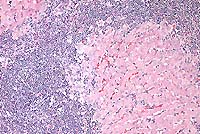

Contributor's Diagnosis and Comments: Liver: Severe chronic diffuse bridging lymphocytic pericholangitis and hepatitis. Pancreas (sections not submitted): Severe chronic diffuse sclerosing lymphoplasmacytic pancreatitis with marked multifocal ductular ectasia.

The findings in this case are consistent with feline progressive cholangitis. According to Lucke and Davies (1984), cats usually present with ascites, jaundice, polyphagia and weight loss; some cats are anorexic. In the same study, cats had unremarkable serum biochemistries with the exception of mildly to moderately increased alkaline phosphatase activities in 12 of 21 cats, and mild to marked increases in conjugated bilirubin in 6 cases.

Gross findings of feline progressive cholangitis consist of a normal to enlarged liver, an enhanced reticular pattern and variably present hepatic nodular change. Histologically, there is prominent lymphocytic infiltration and fewer numbers of other leukocytes. Other changes can include bile duct destruction and/or proliferation, and fibrosis with vascular changes similar to those seen in cirrhosis.

Due to the normal anatomic fusion of the feline pancreatic and biliary ducts proximal to the duodenum, feline hepatobiliary disease may be seen in conjunction with chronic pancreatitis and obstruction. The cat in this case had a severe sclerosing pancreatitis of unknown etiology.

Conference Note: Feline cholangitis/cholangiohepatitis has been described as a disease complex including three characteristic histologic lesions, each presumably reflecting progressive stages of one disease.4 In this report, suppurative cholangitis/cholangiohepatitis, characterized by periportal and hepatic parenchymal infiltration of neutrophils with bile duct hyperplasia, mild fibrosis, and filling of bile ducts with inflammatory cellular debris, was considered the earliest of the three lesions. Long-term inflammation associated with progression of this condition reportedly led to nonsuppurative cholangitis/cholangiohepatitis, with the characteristic histologic findings of lymphocytic and plasmacytic periportal inflammation, bile duct hyperplasia, and periportal fibrosis. Biliary cirrhosis, with severe portal fibrosis, bile duct hyperplasia, nodular hepatic hyperplasia, and a variable degree of chronic inflammation, was presumed to be the end-stage result of long-term cholangiohepatitis in some cats.

In a recent retrospective study, Gagne et al5 described three subclassifications of feline inflammatory liver disease based on the predominant cell type within portal areas, i.e. lymphocytic-plasmacytic, neutrophilic, and mixed. Lymphocytic portal hepatitis was characterized by portal infiltration of lymphocytes and plasma cells, without neutrophils or macrophages. Inflammation was restricted to the portal area and did not extend into hepatic parenchyma. Lymphoid follicles were occasionally found. Bile duct proliferation and portal or portal-bridging fibrosis were present in most cases, but neither biliary epithelial degeneration nor inflammatory cells in bile ducts was seen. Cats with neutrophilic portal hepatitis had primarily neutrophils, with varying numbers of lymphocytes and plasma cells, present within portal areas. Periportal hepatocellular necrosis was a common finding, as was bile duct epithelial degeneration, necrosis, inflammatory cell infiltrate, and duct proliferation. Portal and portal bridging fibrosis was common. Cats with mixed portal hepatitis had approximately equal numbers of lymphocytes/plasma cells and neutrophils. In this third group of cats, associated histologic changes were similar to those with predominantly neutrophilic portal infiltrates. The authors propose using the term lymphocytic portal hepatitis for those cases characterized by lymphocytic/plasmacytic inflammation confined to the portal areas, and that hepatitis characterized by cholangitis and portal neutrophilic infiltrates with or without lymphocytes and plasma cells be termed cholangiohepatitis.